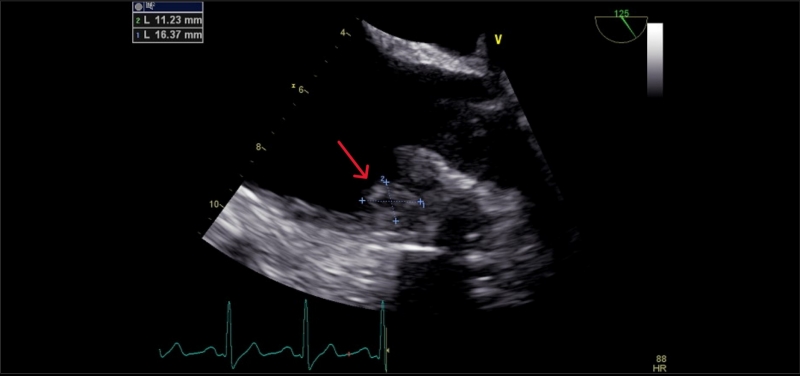

Suverénní diagnostickou metodou síňových trombů je jícnová echokardiografie. Alternativou je srdeční magnetická rezonance a CT, avšak právě výpočetní tomografie s sebou nese limitace ve formě nedostatečné distribuce kontrastní látky v oblastech krevní stázy. Následující kazuistika pojednává právě o nálezu izolované trombózy pravé aurikuly srdeční u pacienta po multimodální léčbě maligního mezoteliomu. Trombus byl diagnostikován jako vedlejší nález při PET/CT a následně potvrzen jícnovou echokardiografií.